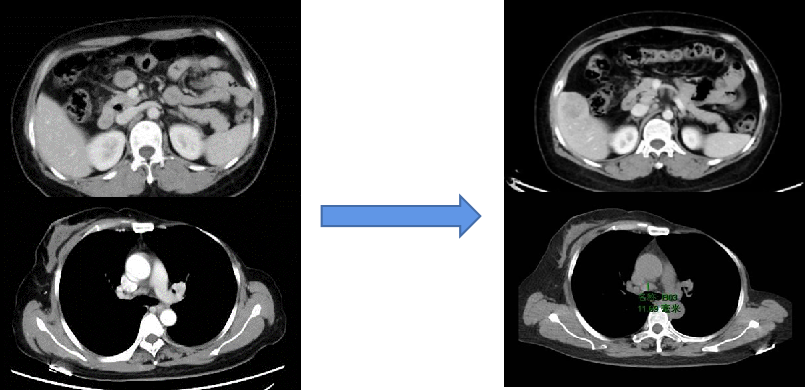

图3A

图3B